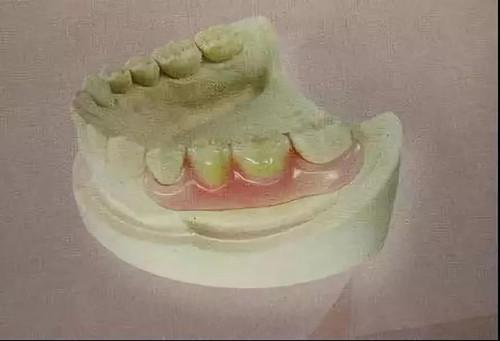

03.过渡性修复体

过渡性修复体是种植全口义齿咬合重建中维持和稳定颌位关系必不可少的重要环节。其作用:一是相当于功能矫治器,用于调整肌张力,让升颌肌群收缩的长度适应新的OVD;二是可修复缺失牙,恢复一定的咀嚼功能、发音功能和容貌;三是作为诊断性咬合设计装置,为永久性修复体的设计提供重要信息。